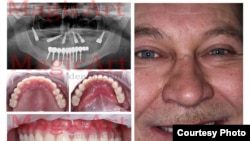

İmplant dişlər

Diş implantasiyanın qiymətləri də kəskin fərqlənir. Belarusda yeni dişin qiyməti 550 dollardısa, ABŞ-da bu rəqəm 2 min 500 dollardır. Belarusa gələn bəzi turistlər dörd, ya beş yeni diş qoydururlar.